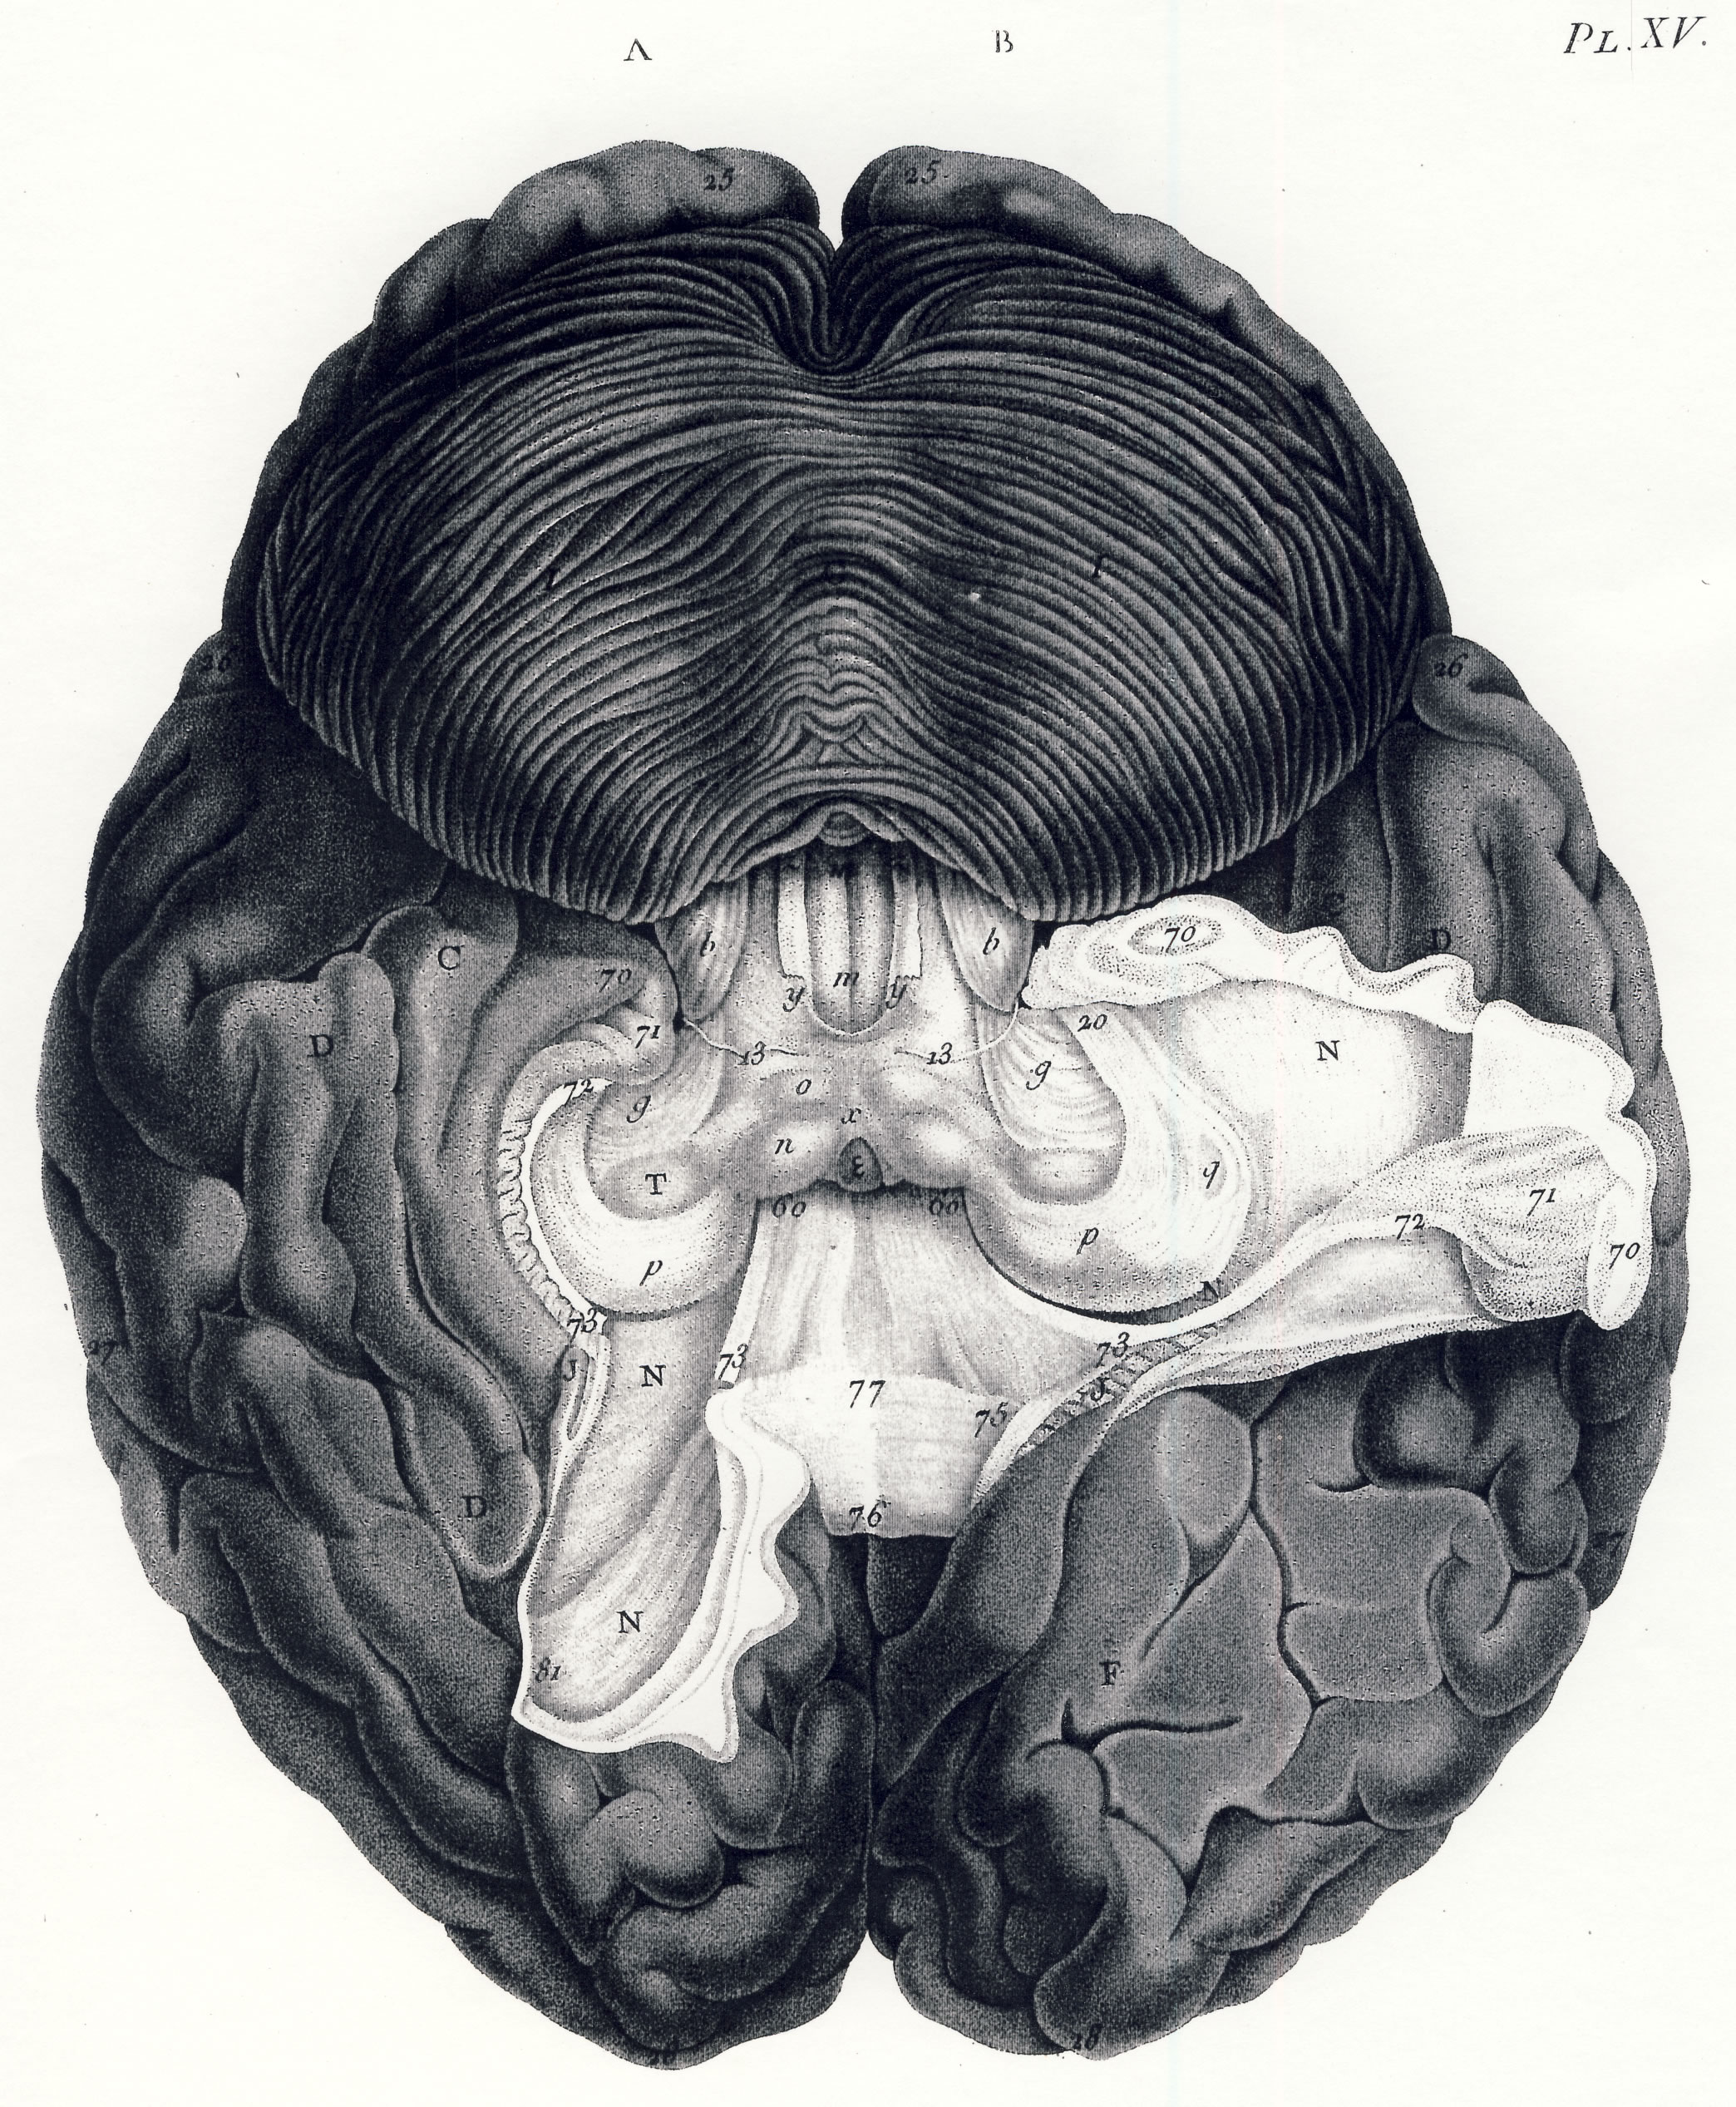

Gall: Plates

Gall, F. J. (1818). Anatomie et physiologie du système nerveux en général, et du cerveau en particulier, Avec des observations sur la possibilité de reconnoître plusieurs dispositions intellectuelles et morales de l´homme et des animaux, par la configuration de leurs têtes.

Librairie Grecque-Latine-Allemande, Vol. 3, I-XXXV u. 1-379 100 planches.